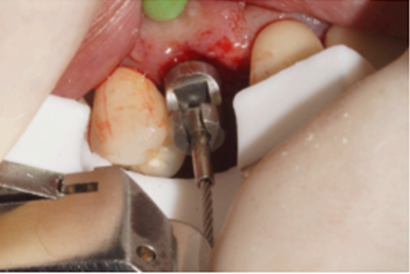

O caso clínico a seguir irá descrever o sucesso dessa nova realidade. Paciente J.C., de 65 anos de idade, do sexo masculino, compareceu em minha clínica com o elemento 13 fraturado (Figura 1). Após análise criteriosa da tomografia, foi planejada a exodontia e a instalação imediata do implante seguindo as novas tendências no posicionamento tridimensional, isto é, a melhor posição no rebordo na relação dento alveolar (Figura 2). Foi realizada a terapia medicamentosa com a administração de Amoxicilina 500 mg, de oito em oito horas durante sete dias, iniciando um dia antes do procedimento, e o uso de anti-inflamatório após a cirurgia, durante três dias. A exodontia foi realizada de forma atraumática, como sugerido na literarura (Figuras 3 e 4) e foi realizada a fresagem para a instalação de um implante Due Cone Implacil De Bortoli (conexão morse) de 3.5 x 13 mm, que foi estabilizado a 46 Ncm (Figuras 5, 6 e 7). Após a instalação, o gap foi preenchido com biomaterial, um cicatrizador de 5.5 X 3.5 mm (diâmetro/altura) foi instalado e o tecido foi suturado ao seu redor, protegendo assim o biomaterial (Figura 8).

Figura 3 – Dispositivo para exodontia

Figura 4 – Exodontia atraumática